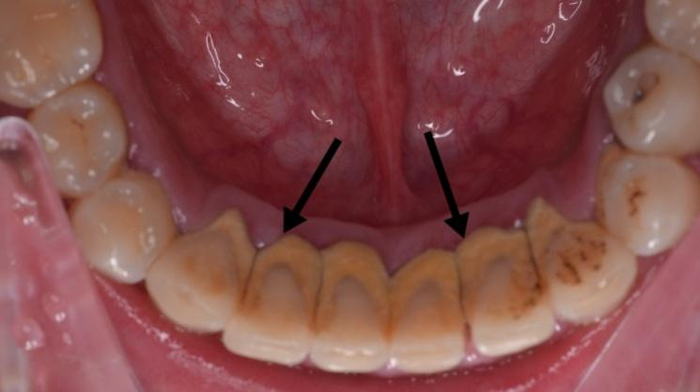

牙周医生在洗牙时发现,下颌前牙内侧、下颌磨牙内侧往往是牙结石的“重灾区”。

除了“优越”的地理位置让食物残渣容易在这里堆积之外,在下门牙附近开口的唾液腺导管也会因分泌唾液,而参与牙结石的产生。

因此刷牙时,刷干净牙齿的内侧面也很重要!